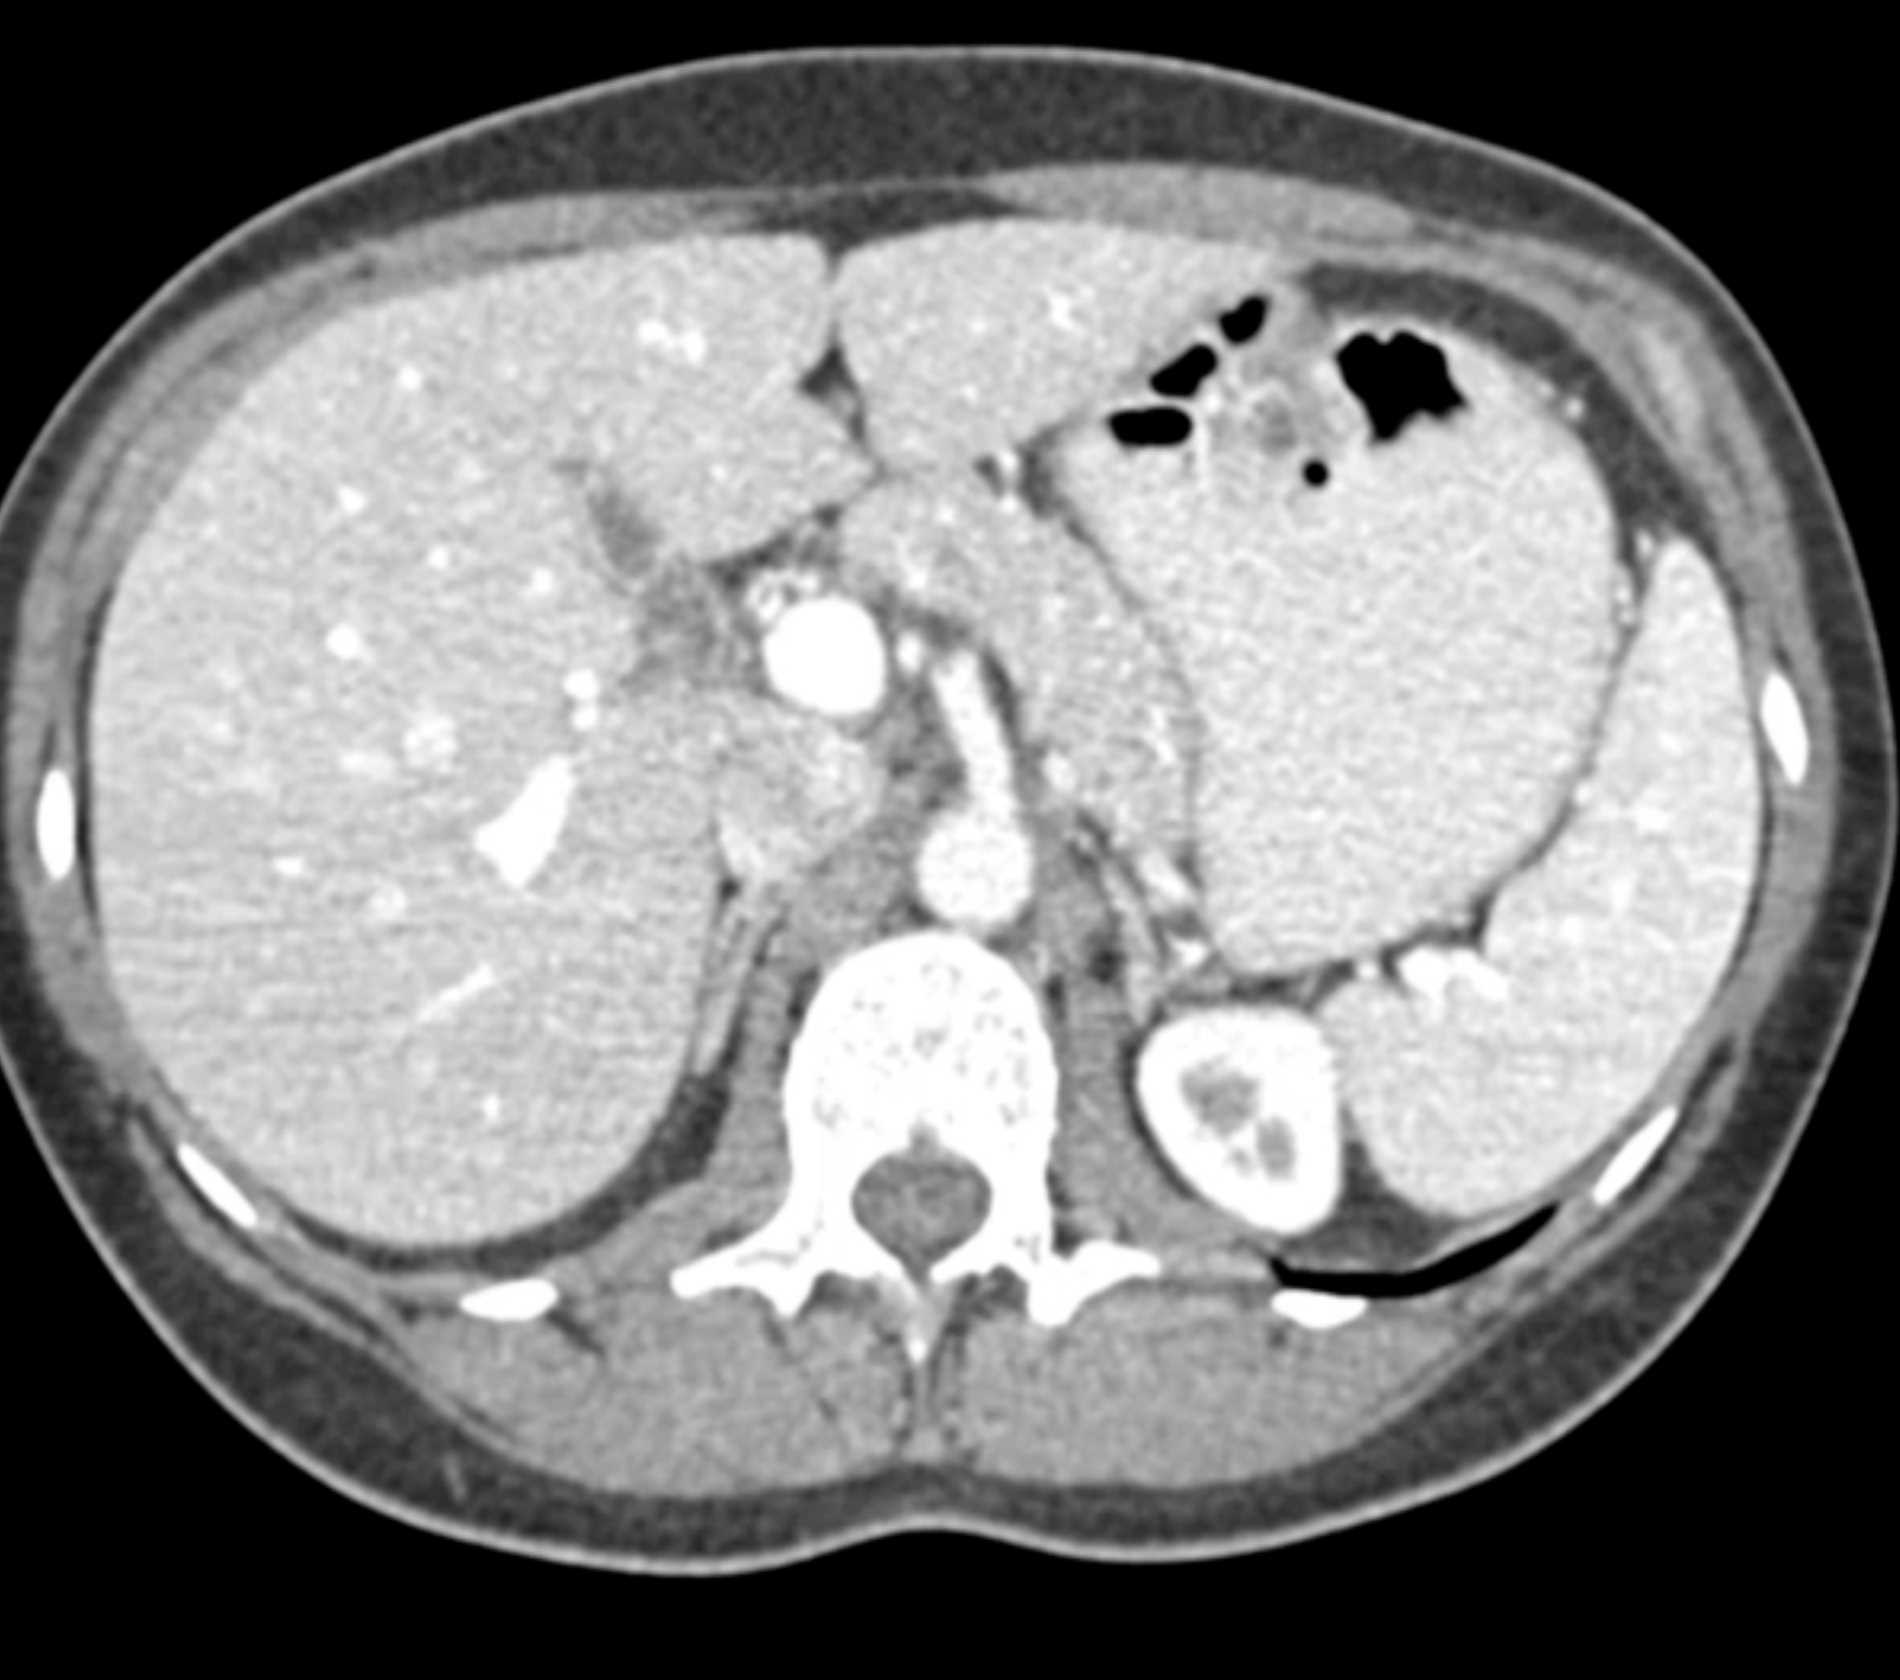

Multiple Gastric GIST Tumors with Spread to Nodes (Carney-Stratakis Syndrome)